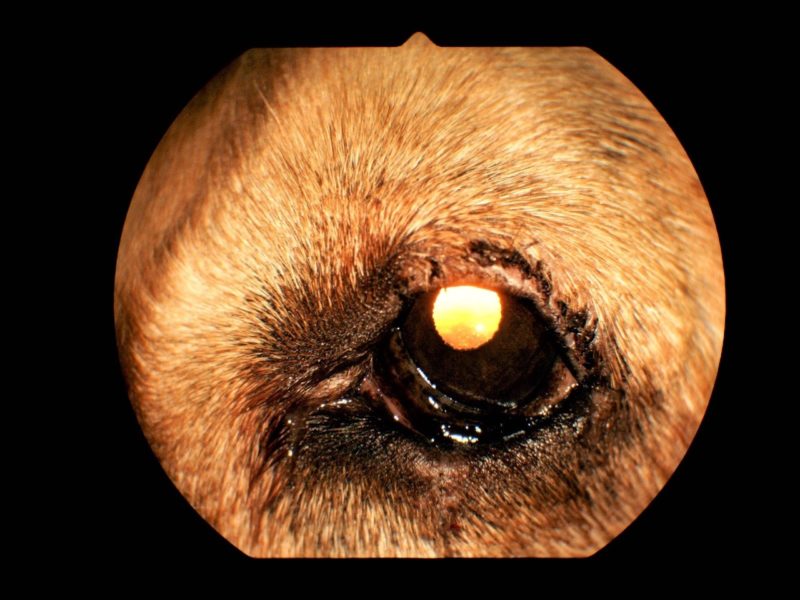

Die Ursache für diese Symptome ist eine multifaktorielle Lidfehlstellung bei „Murphy“. Beide Augen wiesen eine zu große Lidspalte (Makroblepharon) auf. Dadurch ergaben sich zum einen ein ungenügender Lidschluss mit hängenden Unterlidern und chronischer Reizung der Bindehaut und der Hornhaut. Zum anderen waren die Oberlider beidseits aufgrund einer fortgeschrittenen Bindegewebsschwäche auf beiden Seiten hängend und rechts zudem eingerollt. Dies führte rechts zu einer massiven Reizung der Hornhaut durch die Fellhaare (Trichiasisreizung, Abb. 1) mit einem sehr schmerzhaften Defekt in der Hornhaut (Ulkus korneae, Abb. 2). Diese Form des eingerollten oder hängenden Oberlides entsteht durch eine altersbedingte erworbene Bindegewebsschwäche.